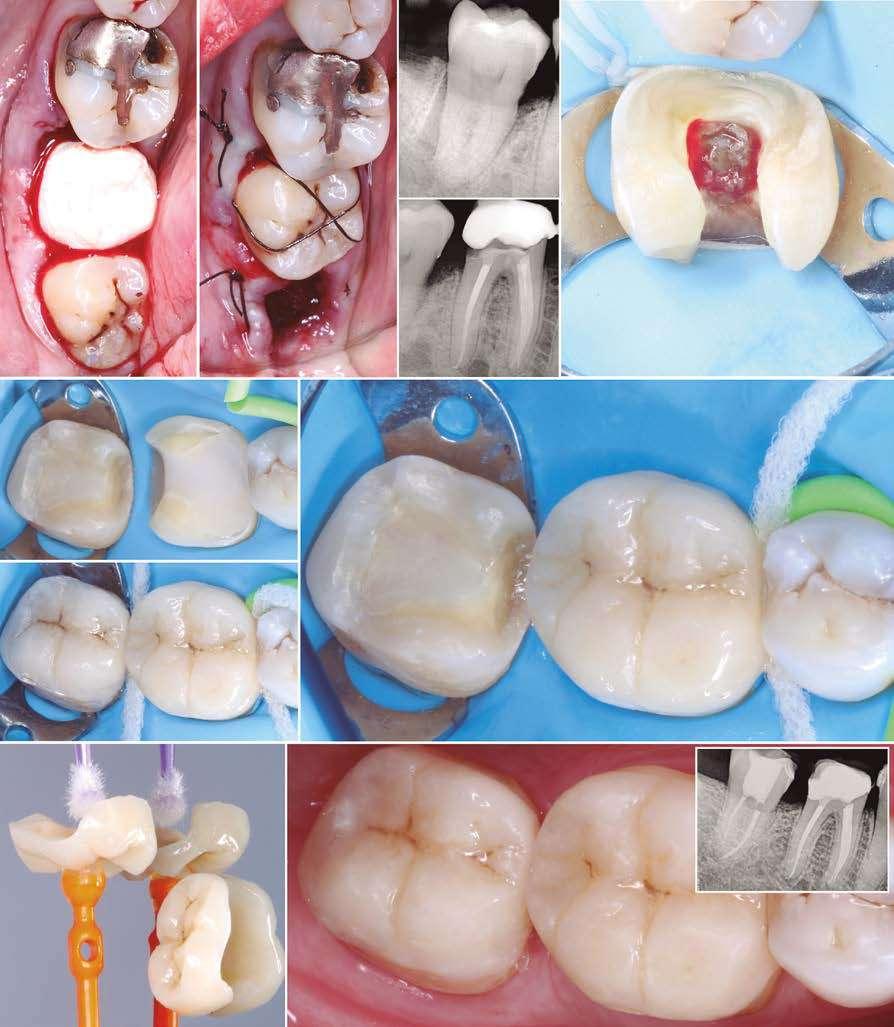

Figuras 3 y 4 . Corte del Cone-beam dental tras la exodoncia y regeneración del alveolo con Endoret-PRGF cuatro semanas después. Podemos observar la atrofia ósea en sentido vertical de la zona con una altura máxima de 3 mm. La planificación como podemos visualizar será para la realización de una elevación transcrestal mínima y la colocación de un implante extracorto.

Figuras 5 y 6. Inicio de fresado de la cortical inferior del seno maxilar con la fresa de corte frontal.

Figuras 7 y 8. Despegamiento de la membrana para comenzar la elevación transcrestal.

Figuras 9 y 10. Inserción de membrana de fibrina como material de relleno en el neo-alveolo y colocación del implante.

Figura 11. Colocación de la corona con el transepitelial unitario 6 meses tras la cirugía.

Figura 12. Mantenimiento de la altura ósea lograda y de la estabilidad del implante al año de carga visualizada en cone-beam.

Figura 13. Estabilidad del tratamiento a los 7 años. No existe pérdida ósea asociada ni problemas relacionados con la prótesis.